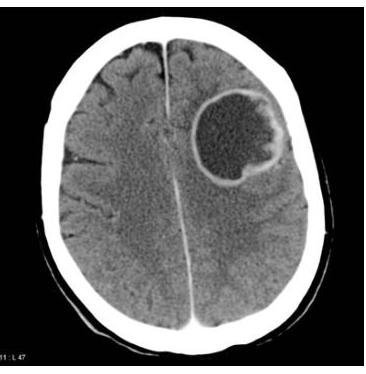

# **TUMORES DEL SNC** ## **DEFINICIÓN** Los tumores cerebrales representan un grupo grande y heterogéneo de neoplasias cuyo factor común es un desequilibrio que se produce en relación con la proliferación/muerte celular debido a la acumulación de células provocada por mecanismos genéticos o epigenéticos. ## **EPIDEMIOLOGÍA** - Los meningiomas son los tumores primarios más frecuentes. - En cuanto a tumores generales, las **METÁSTASIS** son los tumores cerebrales más frecuentes. - El cáncer de pulmón de células pequeñas es la metástasis a cerebro más frecuente. - Las neoplasias cerebrales representan 15-20% de los tumores en infancia y adolescencia. - Pediátricos: **FOSA CRANEAL POSTERIOR**, **TALLO** y **CEREBELO** (60% de los tumores). - Adultos: **SUPRATENTORIAL**. - El tamaño de la lesión **NO SE RELACIONA CON EL PRONÓSTICO**. - El Glioblastoma Multiforme es el tumor primario más común en el adulto (**MAL PRONÓSTICO**). ## **FACTORES DE RIESGO** - Genéticos (NFM 1 y 2, Esclerosis Tuberosa, Ataxia Telangiectasia, Sx Von Hippel-Lindau, Sx Sturge-Weber) - Inmunológicos - Radiación **IONIZANTE** (Radiografías, TAC, Hemodinamia) - Exposición a hidrocarburos aromáticos - Neurofibromatosis ## **CLÍNICA** - **CEFALEA** (es el síntoma más común). - Característica: Que lo despierta en la noche. - Náuseas/vómitos - Focalidad neurológica - Alteración de la personalidad - Nistagmo - **HIPERTENSIÓN INTRACRANEAL**: **CEFALEA MATUTINA** + **NÁUSEA** + **VÓMITO**. - **SÍNDROME CEREBELOSO**: **VERMIANO** + **ATAXIA TRONCAL** o de la **MARCHA** + **DISMETRÍA** + **DISARTRIA** + **ROTS** pendulares. ## **SÍNDROME DE HIPERTENSIÓN INTRACRANEAL CRÓNICO**: - Puede ser por hidrocefalia, tumores o infección. - Síntomas de un solo lado: Pensar en **CORTEZA CEREBRAL**. - Síntomas bilaterales y pares craneales en contralateral: **TALLO CEREBRAL**. - Síntomas de marcha y nistagmus del mismo lado de la lesión del **CEREBELO**. ## **DATOS DE ALARMA**: **CEFALEA CRÓNICA Y PROGRESIVA**, **VÓMITO RECURRENTE**, **ALTERACIONES VISUALES**, **DISFUNCIÓN ENDOCRINA**, **REGRESIÓN DE HITOS DEL DESARROLLO**, **ALTERACIÓN EXAMEN NEUROLÓGICO**. - **PAPILEDEMA** + **FONTANELA TENSA** + **VÓMITO** + **OJOS EN SOL NACIENTE** (no se pueden levantar). ## **TRIADA DE CUSHING** (**HIPERTENSIÓN INTRACRANEANA**) Sucede cuando el efecto de masa aumenta la PIC: **HIPERTENSIÓN** + **BRADICARDIA** + **ALTERACIONES RESPIRATORIAS**. # **DIAGNÓSTICO** ## 1ra elección: **EXPLORACIÓN NEUROLÓGICA** Debe realizarse un examen neurológico exhaustivo ya que en más del \mathbf{95 \%} de los casos se encuentra alguna alteración neurológica añadida a los síntomas que motivaron la consulta. ## **GOLD STANDARD**: **RMN CON GADOLINIO** Ante la sospecha de tumor cerebral, el estudio de imagen más importante siempre será **RMN CON GADOLINIO**. ## **TAC** En su modalidad simple o contrastada es una alternativa útil cuando no se cuenta con RMN y cuando es indispensable descartar **HIDROCEFALIA** asociada.  # **MANEJO INICIAL** - Posición neutra. - Elevación 15-30°. - Descompresión abdominal con SNG. - Si hay falla respiratoria, **INTUBACIÓN ENDOTRAQUEAL** de secuencia rápida. ## **ESTADO EPILÉPTICO** - **MIDAZOLAM** Fenitoína puede recomendarse en menores de 6 años de forma empírica para evitar la recurrencia. No se recomienda el uso de antiepilépticos profilácticos. ## **MANEJO ANTIEDEMA** ## 1ra e: **DEXAMETASONA IV** - Dosis de 1 mg/kg como dosis de carga y posteriormente 1-1.5 mg/kg dividido en 4 dosis. # **ASTROCITOMA** - Es la neoplasia cerebral más frecuente en **NIÑOS**. A nivel histopatológico aparecen **FIBRAS DE ROSENTHAL** en la tinción hematoxilina-eosina. **LOCALIZACIÓN**: **INFRATENTORIAL** (43%). ## **CARACTERÍSTICAS** - Causan **CRISIS EPILÉPTICAS**. - No captan **CONTRASTE**. - Aparecen en **LÓBULO FRONTAL** y **TEMPORAL**.  | GRADO OMS | GRADO | TRATAMIENTO | | :--: | :-- | :-- | | Grado I | Bajo Grado | **CIRUGÍA** | | Grado II | Bajo Grado | **CIRUGÍA**. Radioterapia si no es resecable. Quimioterapia en recurrencias. | | Grado III | **ANAPLASIA** y **ACTIVIDAD MITÓTICA** | **CIRUGÍA** + **RT** + **QT**. | | Grado IV | **PROLIFERACIÓN MICROVASCULAR** y **NECROSIS** | | ## **OLIGODENDROGLIOMA** ## **CARACTERÍSTICAS** Es el tumor más **EPILEPTÓGENO**. **LÓBULO FRONTAL**. Histopatología: Aspecto de **HUEVO FRITO**. **TRATAMIENTO**: - **CIRUGÍA** + **QUIMIOTERAPIA**. ## **EPENDIMOMA** ## **CARACTERÍSTICAS** Afecta principalmente la **MÉDULA ESPINAL** y el suelo del \(4^{\circ}\) ventrículo. Es común en **NIÑOS**. **TRATAMIENTO**: - **CIRUGÍA** + **RADIOTERAPIA**.  ## **MEDULOBLASTOMA** ## **CARACTERÍSTICAS** - Es la neoplasia más frecuente en **MENORES DE 5 AÑOS**. - Asociación con Síndromes de **LI-FRAUMENI** y **TURCOT**. - Localizado en el techo del \(4^{\circ}\) ventrículo. Histopatología: **ROSETA DE HOMER-WRIGHT**. ## **TRATAMIENTO** - **CIRUGÍA** + **QUIMIOTERAPIA** + **RADIOTERAPIA**. ## **MENINGIOMA** - \(2^{\circ}\) neoplasia más frecuente en el adulto (después del **GLIOMA**). - Típico en **MUJERES** de \(5^{a}\) y \(6^{a}\) década. - Se asocia a **CA DE MAMA** y **TVP**. ## RMN: **COLA DURAL**. ## **TRATAMIENTO** - **CIRUGÍA**. ## **GERMINOMA** - Es el tumor **PINEAL** más frecuente. - Se acompaña de **DIABETES INSÍPIDA** / **PUBERTAD PRECOZ**. - Es un tumor **INVASOR** y causa **HIDROCEFALIA**. ## **TRATAMIENTO** - **RADIOTERAPIA**.  | TUMOR | LOCALIZACIÓN | DIAGNÓSTICO | DATOS | | :--: | :--: | :--: | :--: | | ASTROCITOMA | **INFRATENTORIAL** (43%). **PISO DEL \(4^{\circ}\) VENTRÍCULO**. | RMN: **REALCE EN ANILLO**. | Tumor cerebral más frecuente en **PEDIATRÍA** (<18 años). | | MEDULOBLASTOMA | Localizado en el techo del \(4^{\circ}\) ventrículo. | **PUNCIÓN LUMBAR**: Se buscan células y marcadores específicos preoperatorios. | Tumor más frecuente en **<4 AÑOS**. Tumor embrionario altamente **MALIGNO** con tendencia a la **DISEMINACIÓN LEPTOMENÍNGEA**. Asociación con Síndromes de **LI-FRAUMENI** y **TURCOT**. | | OLIGODENDROGLIOMA | **LÓBULO FRONTAL**. | Histopatología: Aspecto de **HUEVO FRITO**. | Es el tumor más **EPILEPTÓGENO**. | | EPENDIMOMA | **MÉDULA ESPINAL** y el suelo del \(4^{\circ}\) ventrículo. Se origina de células ependimarias del sistema ventricular y canal central de médula. | **ROSETAS PERIVASCULARES**. | Lesión **FOSA CRANEAL POSTERIOR**. **EDAD MEDIA**: 5.6 **AÑOS**. | | MENINGIOMA | Tumor localizado en las **MENINGES**. | RMN: **COLA DURAL**. | \(2^{\circ}\) neoplasia más frecuente en el adulto (después del **GLIOMA**). Es el **TUMOR NO MALIGNO** más frecuente en el adulto. Se asocia a **CA DE MAMA** y **TVP**. | | GERMINOMA | **GLÁNDULA PINEAL**. Tumor **INVASOR** y causa **HIDROCEFALIA**. | Asociado a **DIABETES INSÍPIDA** / **PUBERTAD PRECOZ**. | Es el tumor **PINEAL** más frecuente. | # **SÍNTOMAS DE AUMENTO DE PRESIÓN INTRACRANEANA**: 1. **VÓMITOS** (69%). 2. **CEFALEA** (53%). 3. **ATAXIA** (27%). 4. **LATERALIZACIÓN DE CABEZA** (8%). 5. **CONVULSIONES** (6%).

# TUMORES DEL SNC ## DEFINICIÓN Los tumores cerebrales representan un grupo grande y heterogéneo de neoplasias cuyo factor común es un desequilibrio que se produce en relación a la proliferación/muerte celular a factor de la acumulación de células, provocado por mecanismos genéticos o epigenéticos. ## EPIDEMIOLOGÍA - Los meningiomas son los tumores primarios más frecuentes. - En cuanto a tumores generales, las METÁSTASIS son los tumores cerebrales más frecuentes. - El cáncer de pulmón de células pequeñas es la metástasis a cerebro más frecuente. - Las neoplasias cerebrales representan 15-20 % de los tumores en infancia y adolescencia. - Pediátricos FOSA CRANEAL POSTERIOR, TALLO y CEREBELO (60% de los tumores) - Adultos SUPRATENTORIAL. - El tamaño de la lesión NO SE RELACIONA CON EL PRONÓSTICO. - El Glioblastoma Multiforme es el tumor primario más común en el adulto (mal pronóstico) ## FACTORES DE RIESGO - Genéticos (NFM 1 y 2, Esclerosis Tuberosa, Ataxia Telangiectasia, Sx Von-Hipel-Lindau, Sx Sturge-Weber) - Inmunológicos - Radiación IONIZANTE (Radiografías, TAC, Hemodinamia) - Exposición a hidrocarburos aromáticos - Neurofibromatosis CLÍNICA - CEFALEA (es el síntoma más común) - Característica: que lo despierta en la noche - Náuseas/Vómitos - Focalidad Neurológica - Alteración en la personalidad - Nistagmo - Hipertensión Intracraneal: CEFALEA MATUTINA + NÁUSEA + VÓMITO - Síndrome Cerebeloso: Vermiano + Ataxia Troncal o de la Marcha + Dismetría + Disartria + ROTS pendulares. ## SÍNDROME DE HIPERTENSIÓN INTRACRANEAL CRÓNICO: - Puede ser por hidrocefalia, tumores o infección - Síntomas de un solo lado: Pensar en corteza cerebral - Síntomas bilaterales y pares craneales en contralateral: Tallo cerebral - Síntomas de marcha y nistagmus del mismo lado de la lesión del Cerebelo ## DATOS DE ALARMA: cefalea crónica y progresiva, vómito recurrente, alteraciones visuales, disfunción endócrina, regresión de hitos del desarrollo, alteración examen neurológico. - Papiledema + Fontanela Tensa + Vómito + Ojos en sol naciente (no se pueden levantar) TRIADA DE CUSHING (Hipertensión Intracraneana) Sucede cuando el efecto de masa aumenta la PIC Hipertensión + Bradicardia + Alteraciones Respiratorias # DIAGNÓSTICO ## 1ra elección: EXPLORACIÓN NEUROLÓGICA Debe realizarse un examen neurológico exhaustivo ya que en más del \mathbf{9 5 %} de los casos se va a encontrar alguna alteración neurológica agregada a los síntomas que motivaron la consulta. ## GOLD STANDARD: RMN CON GADOLINEO Ante la sospecha de tumor cerebral el estudio de imagen más importante siempre será RMN CON GADOLINIO. ## TAC En su modalidad simple o contrastada es una alternativa útil cuando no se cuenta con RMN y cuando es indispensable descartar hidrocefalia asociada  # MANEJO INICIAL - Posición neutra - Elevación 15-30 - Descompresión abdominal con SNG - Si hay falla respiratoria Intubación Endotraqueal de secuencia rápida ## ESTADO EPILÉPTICO - MIDAZOLAM Fenitoína puede recomendarse en menores de 6 años de forma empírica para evitar la recurrencia. No se recomienda el uso de antiepilépticos profilácticos. ## MANEJO ANTIEDEMA ## 1rae: DEXAMETASONA IV - Dosis de 1 mg / kg como dosis de carga y posteriormente 1 - 1.5 dividido en 4 dosis. # ASTROCITOMA ## - Es la neoplasia cerebral más frecuente en niños. A nivel histopatológico aparecen Fibras de Rosenthal en la tinción hematoxilina-eosina. LOCALIZACIÓN: INFRATENTORIAL (43%) ## CARACTERÍSTICAS - Causan crisis epilépticas - No captan contraste - Aparecen en Lóbulo frontal y temporal  ## RMN - Realce en Anillo | GRADO OMS | GRADO | TRATAMIENTO | | :--: | :-- | :-- | | Grado I | Bajo Grado | Cirugía | | Grado II | Bajo Grado | Cirugía Radioterapia si no es resecable Quimioterapia en recurrencias | | Grado III | Anaplasia y Actividad Mitótica | Cirugía + RT + QT Cirugía + RT + QT | | Grado IV | Proliferación microvascular y necrosis | | ## OLIGODENDROGLIOMA ## CARACTERÍSTICAS Es el tumor más epileptógeno Lóbulo frontal Histopatología: Aspecto de Huevo Frito Tratamiento: - Cirugía + Quimioterapia ## EPENDIMOMA ## CARACTERÍSTICAS Afecta principalmente la médula espinal y el suelo del 4^{\circ} ventrículo Es común en niños. Tratamiento: - Cirugía + Radioterapia  ## MEDULOBLASTOMA ## CARACTERÍSTICAS - Es la neoplasia más frecuente en MENORES 5 años. - Asociación con Síndromes de Li-Fraumeni y Turcot. - Localizado en el techo del 40 ventrículos. Histopatología: Roseta de Homer-Wright ## TRATAMIENTO - Cirugía + Quimioterapia + Radioterapia ## MENINGIOMA - 20 neoplasia más frecuente en el adulto (después del Glioma) - Típico en mujeres de 5o y 6o década - Se asocia a Ca de Mama y TVP ## RMN: Cola Dural - ## TRATAMIENTO - Cirugía ## GERMINOMA - Es el tumor PINEAL más frecuente - Se acomaña a diabetes insípida/pubertad precoz - Es un tumor invasor y causa hidrocefalia ## TRATAMIENTO - Radioterapia  | TUMOR | LOCALIZACIÓN | DIAGNÓSTICO | DATOS | | :--: | :--: | :--: | :--: | | ASTROCITOMA | INFRATENTORIAL (43 %) PISO DEL 4^{\circ} VENTRICULO | RMN: Realce en Anillo | Tumor cerebral más frecuente en pediatría ( <18 años) | | MEDULOBLASTOMA | Localizado en el techo del 4^{\circ} ventrículos. | PUNCIÓN LUMBAR: Se buscan células y marcadores específicos preoperatorios. | Tumor más frecuente en <4 años Tumor embrionario altamente maligno con tendencia a la diseminación leptomeníngea Asociación con Síndromes de Li- Fraumeni y Turcot. | | OLIGODENDROGLIOMA | Lóbulo frontal | Histopatología: Aspecto de Huevo Frito | Es el tumor más epileptógeno | | EPENDIMOMA | Médula espinal y el suelo del 4^{\circ} ventrículo Se origina de células ependimarias del sistema ventricular y canal central de médula | Rosetas perivasculares | Lesión FOSA CRANEAL POSTERIOR EDAD MEDIA: 5.6 AÑOS | | MENINGIOMA | Tumor localizado en las meninges. | RMN: Cola Dural | 2^{\circ} neoplasia más frecuente en el adulto (después del Glioma) Es el TUMOR NO MALIGNO más frecuente en el adulto. Se asocia a Ca de Mama y TVP | | GERMINOMA | Glándula Pineal Tumor invasor y causa hidrocefalia | Asociado a Diabetes Insípida/pubertad precoz | Es el tumor PINEAL más frecuente. | # SÍNTOMAS DE AUMENTO DE PRESIÓN INTRACRANEANA: ## 1. Vómitos 69% 2. Cefalea 53 % 3. Ataxia 27 % 4. Lateralización de Cabeza 8 5. Convulsiones 6 %